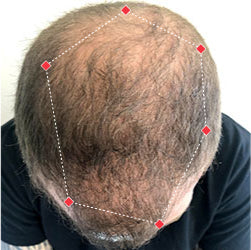

Indications for Use

The iRESTORE Hair Growth System Elite is indicated to promote hair growth in males who have Norwood-Hamilton Classifications of IIa to V and in females who have Ludwig-Savin Classifications I to II, and in both with Fitzpatrick Skin Phototypes I to IV. In other words, iRESTORE is not intended for people who are bald or have advanced hair loss.

Read more in our user manual for Indications of Use, Contraindications, Warnings, and Precautions to find out if iRESTORE is suitable for you.

Laser therapy works to reactivate thinning and dormant hairs. For completely bald areas of the scalp, there may be no way to promote hair regrowth. If you still have hair follicles, laser therapy may be beneficial to you.

Not sure? Email us to have our specialists evaluate your scalp conditions to see if iRESTORE is suitable for you.